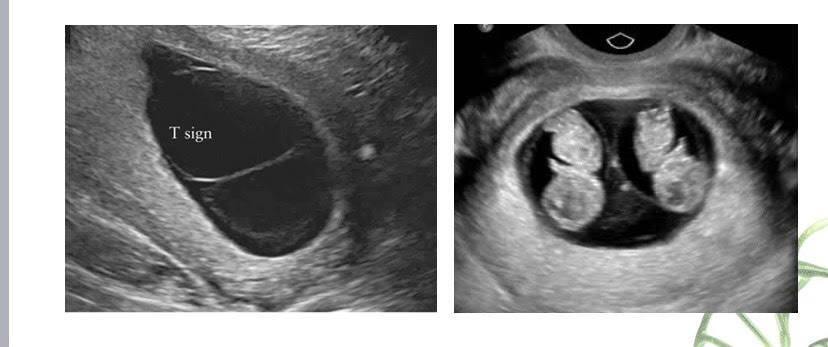

Tuy nhiên, mới đây, Bệnh viện Phụ Sản Hà Nội đã tiếp nhận một trường hợp: Thai phụ 23 tuổi mang thai lần đầu, thai tự nhiên. Kết quả siêu âm cho thấy chung một bánh rau, hai buồng ối từ tuần thai thứ 8.

Thai phụ đến đơn vị can thiệp bào thai - Bệnh viện Phụ Sản Hà Nội thăm khám ở tuần thai 16 vì có một thai phù. Sau khi hội chẩn, siêu âm và chọc ối phát hiện thai A phù thai, giới tính siêu âm là nữ, kiểu gen nữ Turner (45,X).

Hình ảnh trường hợp thai nhi bất thường. (Ảnh: BV)

Còn thai B bình thường về mặt hình thái và giới tính trên siêu âm là nam, kiểu gen nam (46,XY). Các xét nghiệm di truyền chuyên sâu khác cũng đã được thực hiện và chứng minh rằng 2 thai này chung một trứng nhưng có kiểu gen khác nhau.